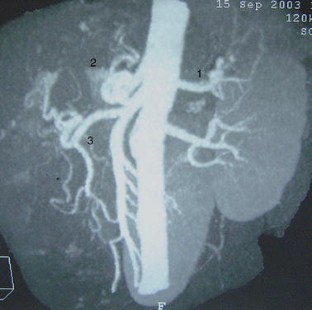

A variation in liver vascularization was discovered in a 50-year-old man. A single common hepatic artery was found to be responsible for vascularization of the entire liver. This artery was unusual in that it formed the first branch of the superior mesenteric artery, crossing the portal trunk shortly after its origin, and passed in front of the portal vein to reach the hilum of the liver, where it divided into a right and a left branch. This artery was a true common hepatic artery because a gastroduodenal artery emerged from it 2 cm after its origin. A common hepatic artery originating from the mesenteric artery and passing in front of the portal vein has never been described before. The patient had a second anatomical variation: the left gastric artery and the splenic artery arose directly from the aorta, without celiac trunk separation. This observation confirms the importance of carrying out a precise vascular assessment before all types of hepatic or pancreatic surgery, to identify possible variations in the number or trajectory of hepatic arteries.

Fig. 3